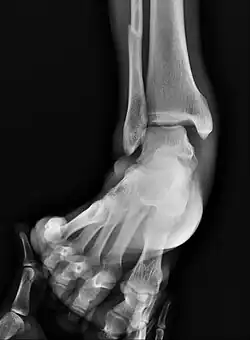

Surgically fixated bimalleolar ankle fracture

The broad goals of treating ankle fractures are restoring the ankle joint to normal alignment, healing the fracture, and preventing arthritis.[9] The stability of the ankle joint often dictates treatment. Certain fracture patterns are stable and are thus treated without surgery similarly to ankle sprains. Unstable fractures require surgery, most often an open reduction and internal fixation (ORIF), which is usually performed with permanently implanted metal hardware that holds the bones in place while the natural healing process occurs. A cast or splint will be required to immobilize the ankle following surgery.[12] Stable ankle fractures with preserved joint alignment may be treated with non-operative measures (splinting, casting, and/or walking boot).[12]